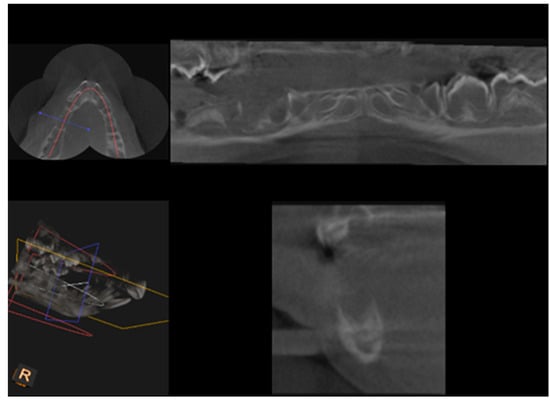

CBCT examination, with a Kodak 3000C 3D system (Kodak Dental Systems, Atlanta, GA, USA), together with Dental Imaging Software ver. 6.12.32 (Kodak Dental Systems, Atlanta, GA, USA), was performed before and immediately after germectomy and then again on the extracted jaws of the piglets after euthanasia with a voxel size of 160 μm, a 0.16 mm space between slices and a field of view of 13 × 10 cm, 90 kV and 4 mA. CT sections were used to assess the width and height of the bone, the thickness of the base plate, the tongue and vestibular side, the dimensions of the marrow cavities, and the height of the mandibular alveolar part. Four measurement planes were determined in the area from the first to the third milky premolars on the dentition side, and then, similarly to the manual measurements, measurement planes were determined for the operated side at the same distance from the line connecting the most distal points of the condylar process and the mandibular angle, in a line parallel to the lower edge of the mandibular shaft. Figure 3 and Figure 4 show an example of a CT scan image of a piglet’s mandible before (Figure 3) and after surgery (Figure 4) and Figure 5 and Figure 6 are diagrams of the external (Figure 5) and internal measurements (Figure 6) of the mandible of the piglets.

Figure 4.

An image after removal of the dental setae together with the bellows.